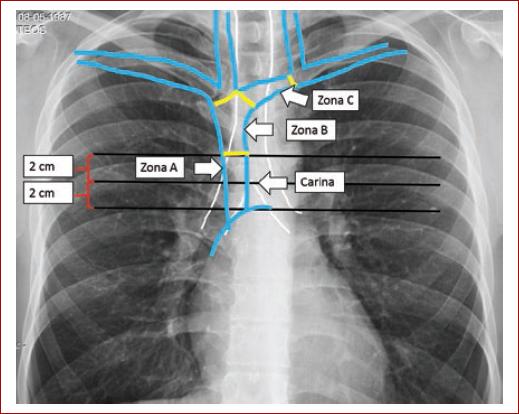

El límite superior de la reflexión pericárdica no se puede ver en la radiografía simple de tórax, pero generalmente se acepta que esté aproximadamente a 0,8 cm por debajo de la carina y el límite inferior a 3 cm por debajo de la carina. Esto ha sido evaluado en cadáveres conservados y frescos. Además, es fácilmente visible incluso en una radiografía de tórax anteroposterior portátil de baja calidad10.

Por lo tanto, la carina ha sido considerada como un hito radiológico para la posición de la punta del CVC (Fig. 1). Las zonas A y B mencionadas en la figura están en relación con la carina. Estas zonas son guías útiles, sin embargo, los catéteres de uso prolongado deben colocarse con precisión bajo fluoroscopia, la posición de la punta del catéter de uso corto debe confirmarse con una radiografía de tórax posterior al procedimiento y para considerarse en posición óptima debe encontrarse a 2 cm de la carina11,12.

Figura 1 Zonas A, B y C donde se puede presentar la punta del catéter venoso central. Zona A, posición optima de punta. En blanco, la tráquea y los bronquios; en azul, la vena cava superior.